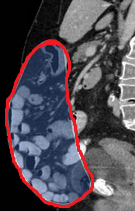

Green shading: Complete occupation of the abdomen by the peritoneal "cocoon" (Courtesy Dr. V. Penopoulos)